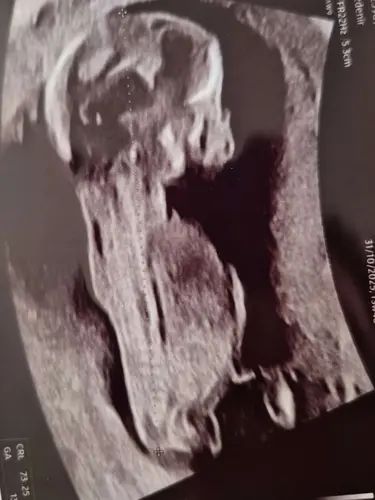

I think its a girl.

Could you olease evaluate the other two pictures below?馃槆

In the 3rd picture it looks

Like a boy. The other 2 girls